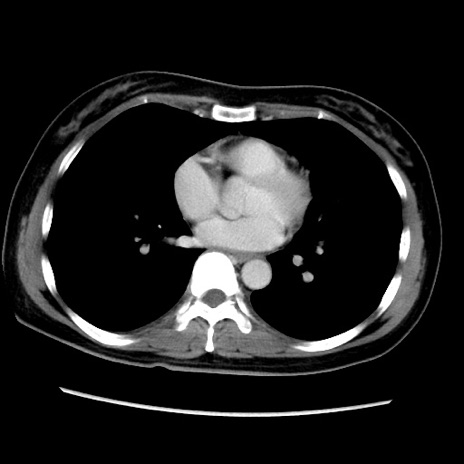

症例39(横断像)

【症例】40歳代女性

【主訴】上下腹部痛

【現病歴】2日目から下腹部痛あり。夜間は痛みで眠れなかった。昨日より上腹部痛と下痢が出現。臥位で痛みは軽快したため、休んでいた。本日になって臥位でも立位でも痛みが強くなってきたため救急要請。

【既往歴】子宮内膜症

【身体所見】部:平坦・軟、左上下腹部に圧痛あり、反跳痛あり。

【データ】WBC 21800、CRP 26.78